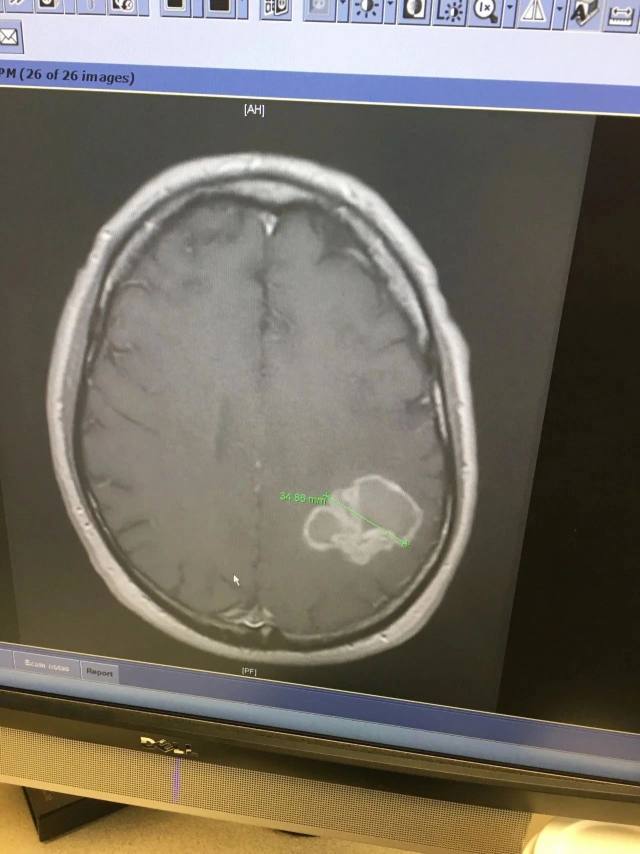

Carpenter 的脑肿瘤图像

CT 扫描发现 Carpenter 的右肺有一个肿块:肺癌已经转移到他的大脑。虽然他从不吸烟。

「我能听到自己说错了,我笑着又向客户重复一遍我想说的,结果这些话又说错了。我把这件事告诉了我的医生,他让我直接去急诊室做核磁共振成像。」在当地医院的急诊室接受检查后,Carpenter 说他注意到检查室外面人潮涌动,人们在窃窃私语。